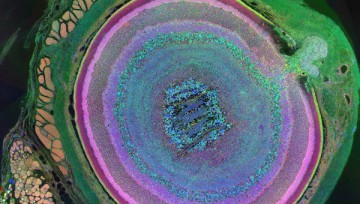

Дендритные клетки — гетерогенные клетки костно-мозгового происхождения, участвующие в работе иммунитета. Их функция — «сканировать» ткани организма для обнаружения вирусов, бактерий и раковых клеток. Они отмечают эти вещества как антигены (враждебные к иммунитету), после чего T-лимфоциты распознают врага и атакуют.

На основе поведения дендритных клеток ученые пытались создать способ борьбы с раком, однако опухоль атаковала клетки таким образом, что те теряли свою функцию. Поэтому авторы искали искусственные пути получения дендритных клеток. Анализируя их факторы транскрипции, они определили три белка (PU.1, IRF8, BATF3), которые необходимы для превращения фибробластов (клеток соединительной ткани) мышей и человека в дендритные клетки.